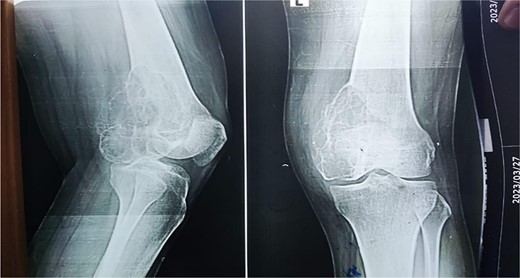

A 28-year-old female patient in her first trimester of pregnancy presented in our outpatient department with a complaint of persistent left knee pain for the past two years accompanied by a marked swelling around the left distal thigh region for the past 6 months. She had a previous X-ray that revealed an aggressive, Enneking stage III osteolytic lesion involving the medial femoral condyle, characterized by a shallow bubble appearance and a narrow zone of transition (Figs 1 and 2). A biopsy of the lesion was undertaken 6 months before the initial presentation and showed an aggressive GCT.

The X-ray shows a distal femur osteolytic lesion with a soap bubble appearance, a narrow zone of transition, a soft tissue component, and a sparing knee joint in the X-ray taken 6 months before pregnancy.